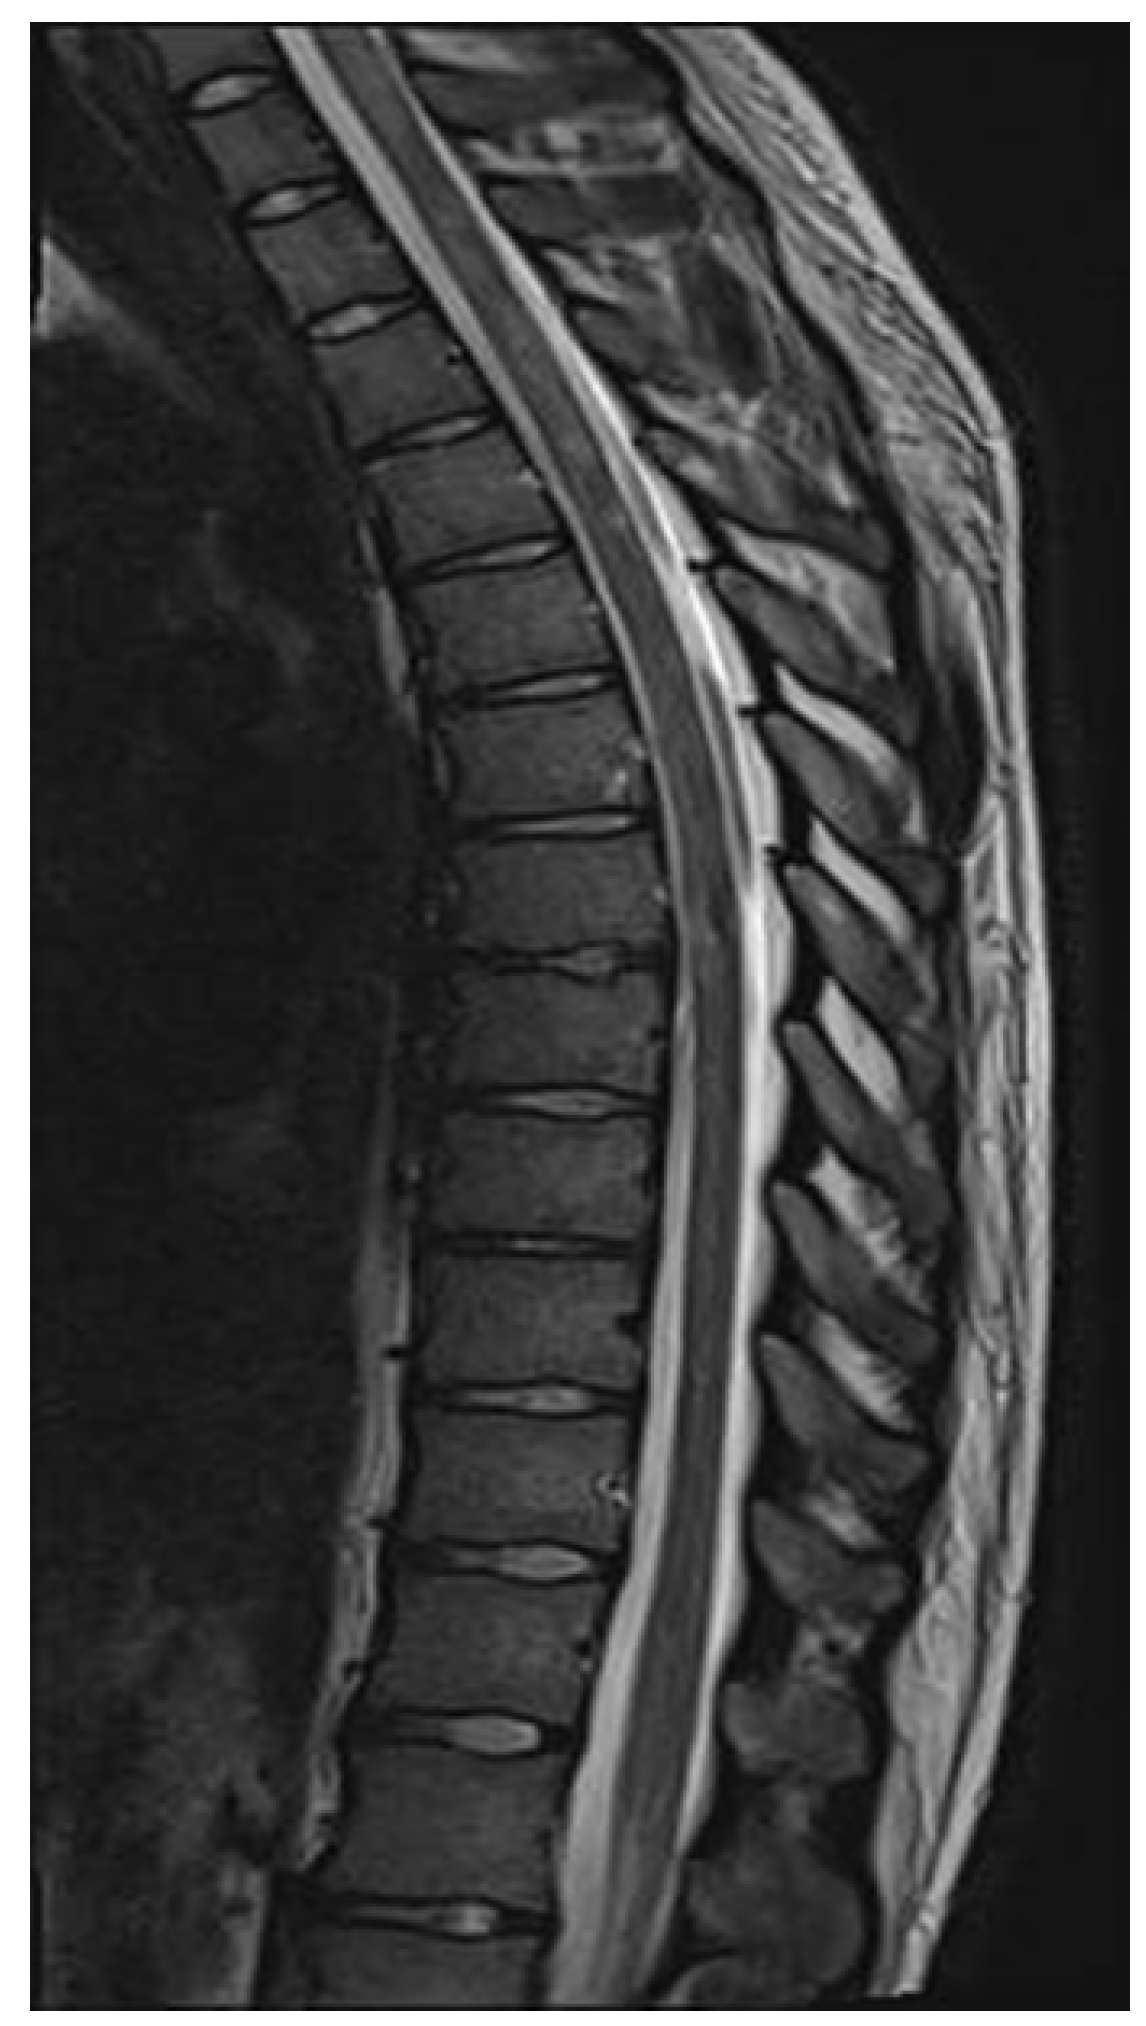

Figure 7.

Spinal cord MRI showing foci of increased signals of thoracic and cervical spine on T2 sequences (March 2022).

ADEM recurrence was recognized. The patient received immunoglobulins (2.0 g IV). After rehabilitation, an improvement in the neurological condition was observed over the next four weeks. The boy returned to school. Subsequently, he reported visual acuity disturbances in the left eye. Therefore, he was hospitalized in the neurology department. On admission, neurological examination showed horizontal nystagmus, lack of abduction in the right eye, dysarthric speech, and cerebellar syndrome. Brain MRI revealed numerous foci of increased signal on T2-weighted and FLAIR sequences, with the largest one occurring in the right cerebellar hemisphere accompanied by the involvement of the peduncle (Figure 5 and Figure 6) and bilateral involvement of the dentate nuclei of the cerebellum. Foci of increased signals on T2-weighted and FLAIR sequences were also found on MRI of the cervical and thoracic spine, meeting the LETM (longitudinally extensive transverse myelitis) criteria (Figure 7). Moreover, an orbital MRI showed “the left optic nerve was thickened to 3–4 mm, with increased T2 signal intensity indicating inflammation; the optic chiasm and right optic nerve were normal” (Figure 8). Again, positive serum anti-MOG antibodies were found in a clear titer of 1:100, while anti-AQP4 antibodies tested negative. Recurrent MOGAD was diagnosed based on the overall picture, and immunoglobulins were administered (a total dose of 2.0 g IV for five days). Oral azathioprine was included in the chronic treatment at a dose of 2 mg/kg body weight and oral methylprednisolone at a dose of 1 mg/kg body weight. After ten weeks (May 2022), right optic neuritis occurred during an attempt at withdrawing glucocorticosteroids. Methylprednisolone was reintroduced at a dose of 5 × 1.0 g intravenously. An MRI of the head revealed two new subcortical foci: one located in the right frontal lobe measuring 13 × 7 mm and another in the left parietal lobe measuring 19 × 14 mm (Figure 9). Additionally, the right optic nerve exhibited blurred outlines (Figure 10) and an increased signal in the central area, along with a marginally enhancing focus in the middle part of the right optic nerve measuring 2 mm in diameter. An ophthalmological consultation was conducted, revealing color vision deficiencies in the right eye across all axes, with no reading capability in the left eye. An OCT examination showed that the retinal nerve fiber layer (RNFL) in the right eye was normal (higher than a month earlier, suggesting a possible inflammatory process), while the left eye exhibited significantly reduced RNFL and ganglion cell count. Atrophy of the left optic nerve was diagnosed. Based on the clinical presentation, recurrent optic neuritis was diagnosed as a manifestation of another MOGAG, correlating with the onset of right optic neuritis following the discontinuation of methylprednisolone. Therefore, a decision was made to increase the dose of azathioprine to 2.5 mg/kg body weight and to maintain methylprednisolone for the following weeks. After the diagnosis of MOGAD with a typical radiological and clinical picture (ADEM, MDEM, recurrent ON) and the initiation of chronic immunosuppressive treatment, no more epileptic seizures were observed. It was decided to discontinue antiepileptic drugs, starting with gradual valproic acid.